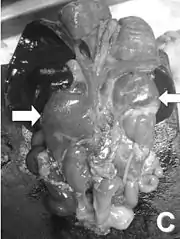

![]() Розтин новонародженого. Стрілки показують збільшені наднирники через їхню гіперплазію Розтин новонародженого. Стрілки показують збільшені наднирники через їхню гіперплазію | |